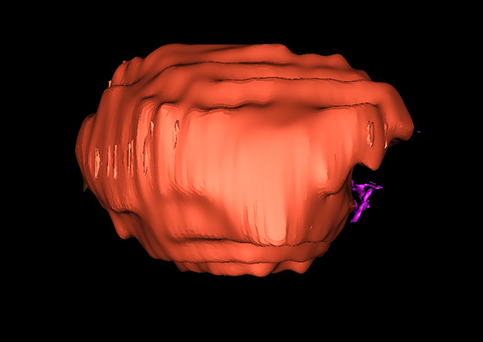

近年来由于数字医学的发展,基于可视化三维重建技术的计算机辅助手术系统极大推进了小儿肝脏肿瘤的精准手术的进步。可以立体透视肝脏解剖、精确掌握肝段的边界、精确测算肝段乃至任意血管所支配的功能体积、准确定位病灶及其与邻近血管的解剖关系,最终对不同手术方案进行比较、筛选和优化。因此,计算机辅助手术规划系统是实现精准肝切除的有力辅助工具,是未来数字外科、精准外科等21世纪外科新理念的重要技术支撑。

计算机辅助手术规划系统具有良好的操作可行性、计算准确性和三维显示效果,可半透明、交互式显示真实的肝内立体解剖关系和空间管道变异,准确计算肝内管道的直径、走行角度,两点间的垂直距离,和任意血管的支配或引流范围等传统二维影像无法获取的信息,有助于实施个体化手术,提高了手术的确定性、预见性和可控性。计算机辅助手术规划系统可直观显示预留肝脏的结构和功能,并可通过虚拟切割功能辅助术者对手术方案进行蹄选和优化,系统评估手术风险和制定对策,改变了部分二维规划的术式和切除范围,使部分二维规划认为不能切除的患者成功手术,提高了手术的根治性、安全性和病变的可切除性,更加符合精准肝脏外科的术前规划要求。详见第11章。

随着计算机技术及影像检查技术的不断发展,以精确的术前影像学和功能评估、精细的手术操作为核心的精准肝切除技术日益受到重视。基于数字医学的计算机辅助手术技术(computer-assisted surgery,CAS)则是实现肝脏精准手术操作的基础。计算机辅助手术系统(CAS)可将术前二维(two dimensional,2D)的CT/MRI影像数据进行三维(three dimensional,3D)重建,建立个体化的肝脏三维解剖模型,清晰显示肝脏内脉管系统的走行及解剖关系,还原病灶与其周围脉管结构的立体解剖构象,准确地对病变进行定位、定性和评估,制定合理、定量的手术方案,实施个体化的肝脏血管取舍分配方案及实施精准肝脏手术。一般认为CAS包括:创建虚拟的患者的图像;患者图像的分析与深度处理;诊断、手术前规划、手术步骤的模拟;术中实时导航。应用本技术后,由于可以更清晰地看出肿瘤的界限,特别是根据肝血管的显影,判断出肿瘤与门静脉及肝静脉的关系以在手术前较准确地估计出手术成功切除的可行性。以往部分根据普通强化CT判断无法手术的病例而被评估为可以成功切除并手术成功。